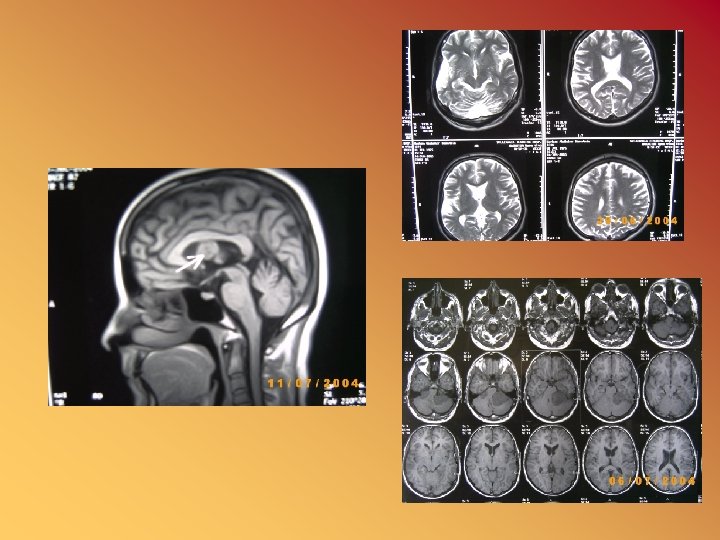

Magnetic Resonance Imaging (MRI)

Advantages • Can select any plane, e. g. coronal, sagittal, oblique. • No ionizing radiation. • More sensitive to tissue changes, e. g. demyelination plaques. • No bone artifacts, e. g. intracanalicular acoustic neuroma

Disadvantages • Limited slice thickness-3 mm. • Bone imaging limited to display of marrow. • Claustrophobia. • Cannot use with pacemaker or ferromagnetic implant.

MR angiography • Rapidly flowing protons can create different intensities and by a special sequence can demonstrate vessels, aneurysms, and AVM

MRI • • Diffusion-weighted MRI Perfusion-weighted MRI Functional MRI MR spectroscopy (N-acetylaspartate, lactate, ATP, and inorganic phosphate)